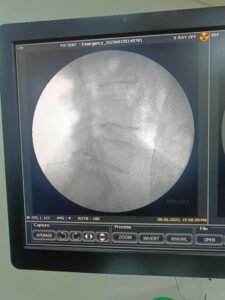

- Epidural Steroid Injections (ESIs): In cases of severe or persistent pain, an ESI may be recommended. This procedure involves injecting a corticosteroid medication directly into the affected area to reduce inflammation and alleviate pain.